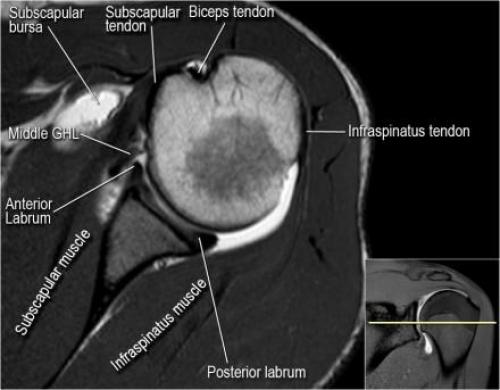

- уровень средней плече-лопаточной связки и передних отделов суставной губы. Поищите комплекс Буффорда. Изучите хрящи.

- вогнутость заднебокового края головки плечевой кости не следует путать с повреждением Хилл-Сакса, поскольку это нормальная форма для данного уровня. Повреждение Хилл-Сакса визуализируется только на уровне клювовидного отростка. В предних отделах мы сейчас на урвоне 3-6 часов. Здесь визуализируются повреждение Банкарта и его варианты.

- обратите внимание на волокна нижней плече-лопаточной связки. На данном уровне так же ищется повреждение Банкарта.